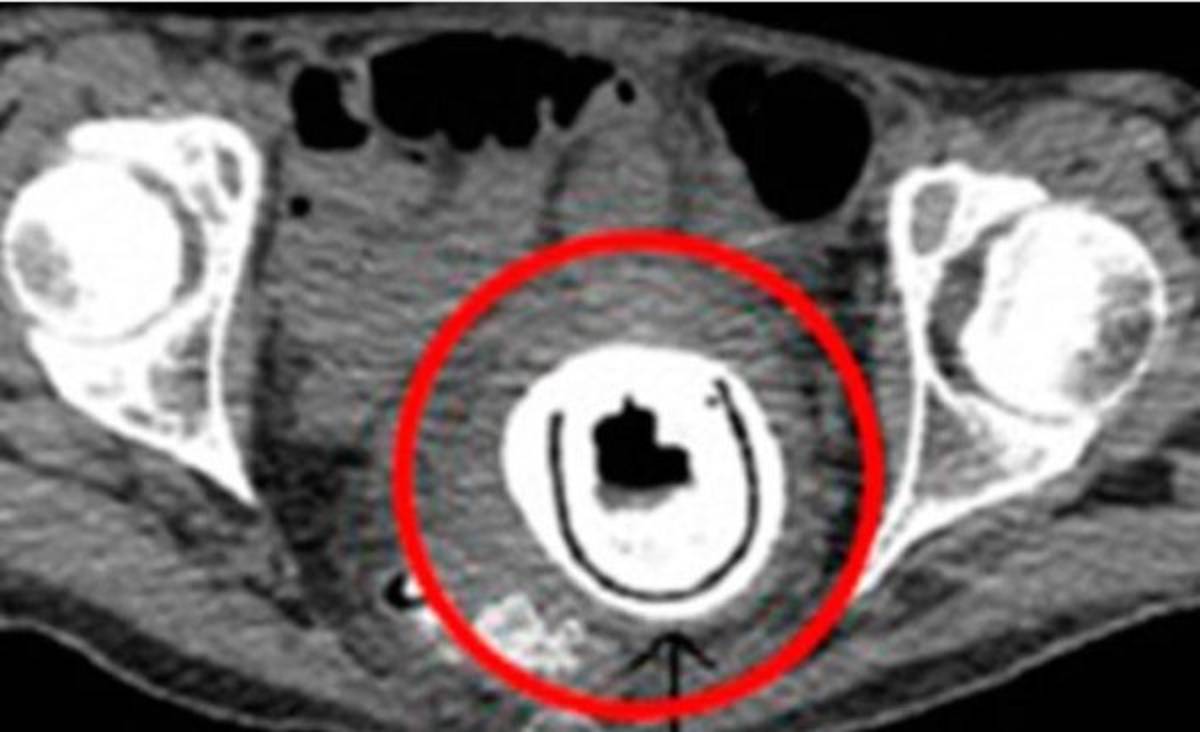

La fémina de 38 años acudió al doctor, quien no podía dar crédito a la imagen que mostraba la radiografía del abdomen, en la que se apreciaba el juguete sexual incrustado.